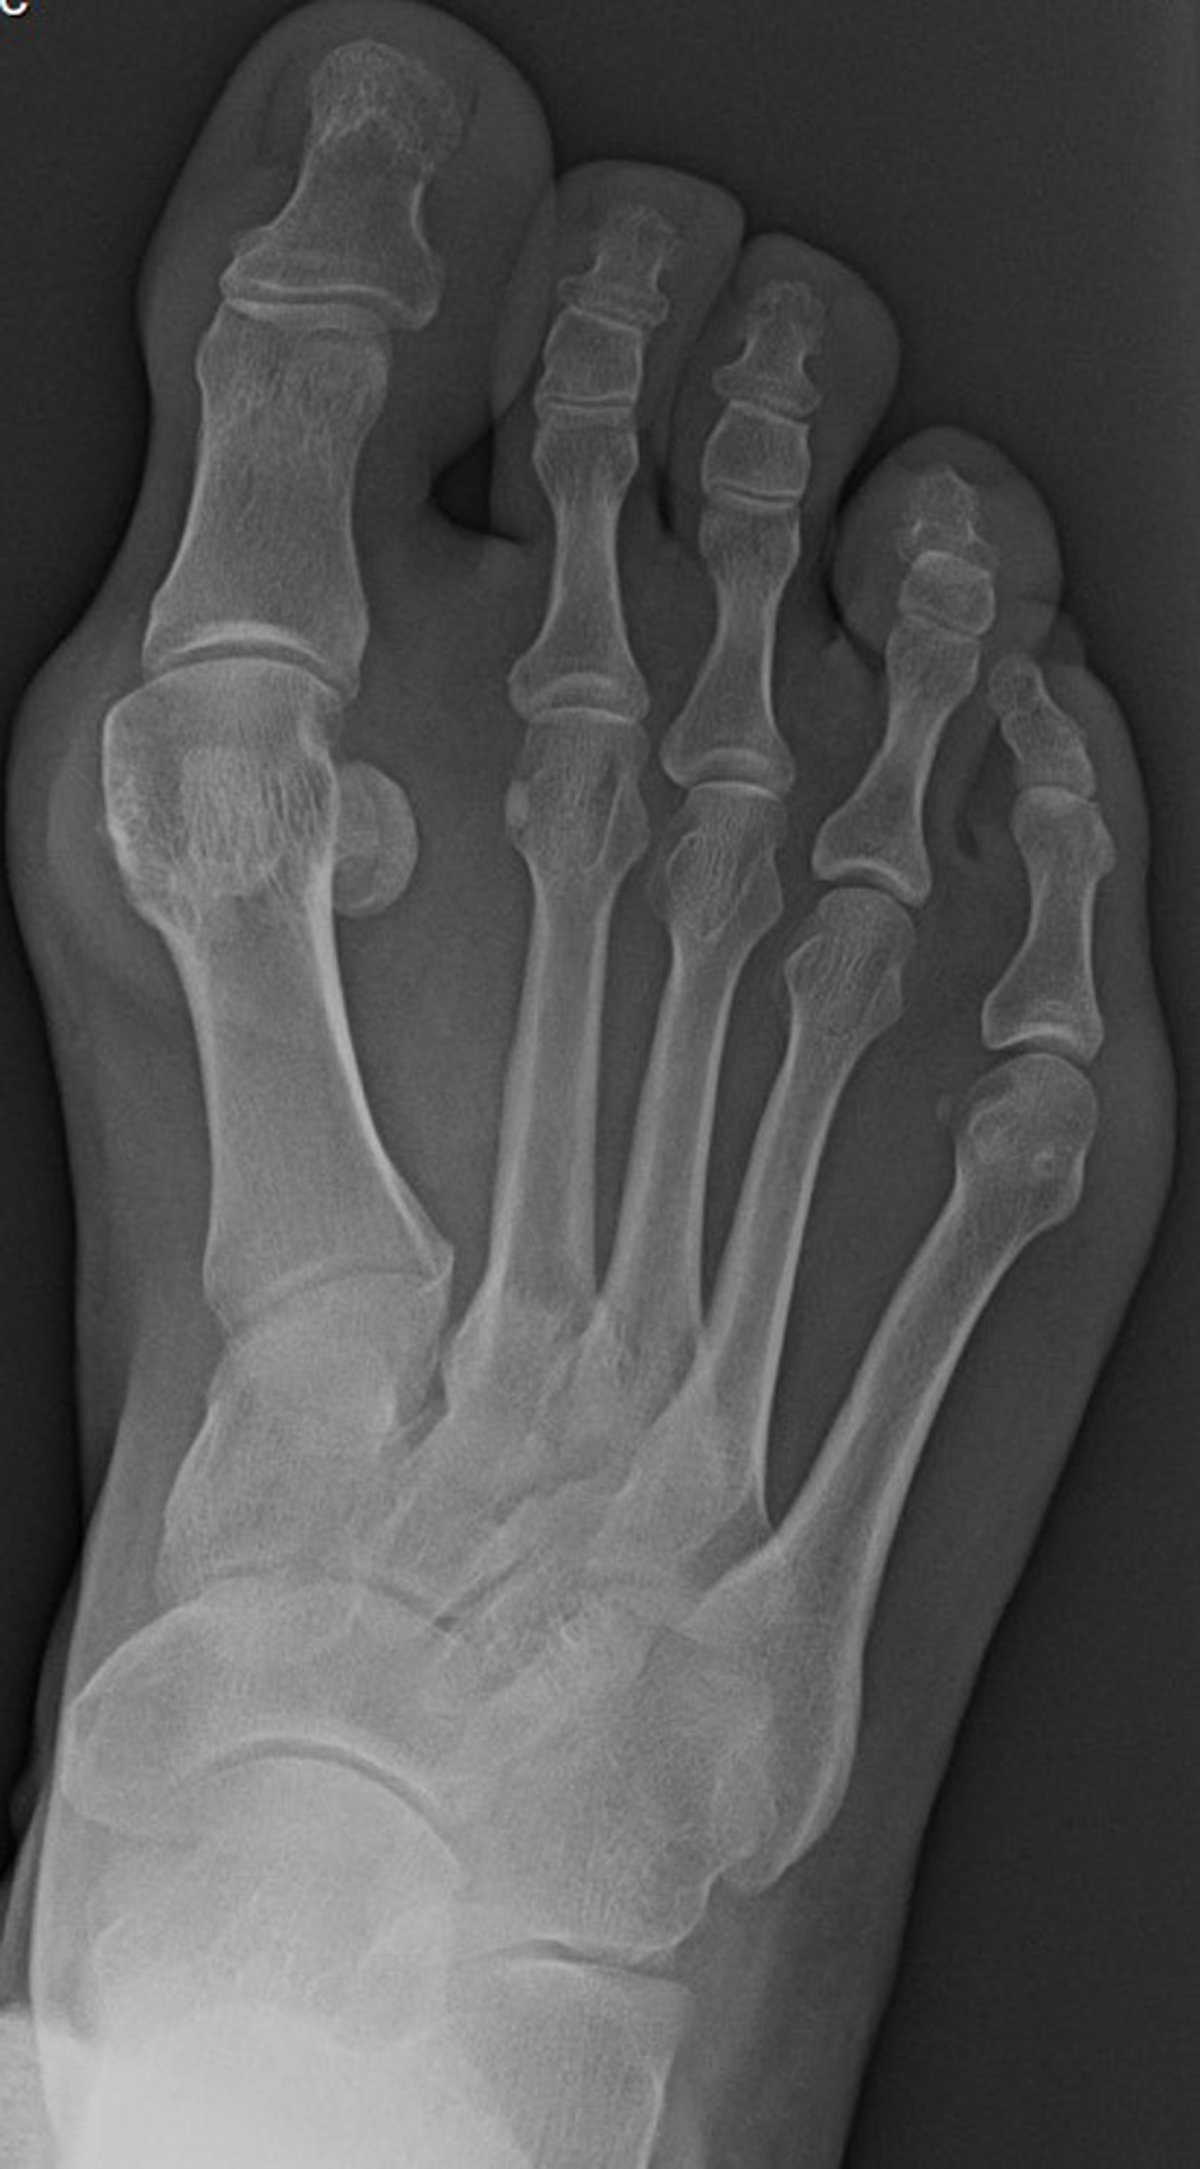

Radiographs are generally not needed for diagnostic purposes, but weight-bearing views may be helpful in determining the extent and severity of damage to the first metatarsophalangeal joint. Suggestive findings include joint space narrowing and bony spurs extending from the metatarsal head or sometimes from the base of the proximal phalanx. On the anteroposterior (AP) radiographic view, the first metatarsal will be deviated medially, which causes the metatarsal head to be prominent in the medial soft tissue. The hallux is angulated laterally and causes excessive wear on the articular surface of the lateral aspect of the metatarsal head. The lateral sesamoid will appear in the intermetatarsal space. The hallux may abut the second digit and, in cases of severe deformity, the hallux may overlap or underlap the second toe.